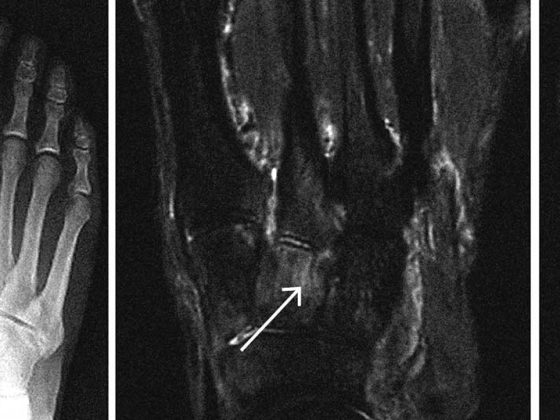

header_maquiera

• Akute oder langsam zunehmende Schmerzen

Häufige Fussprobleme bei Sportlern

• Fortbildung

• Orthopädie

• Rx

• Sportmedizin

Weiterlesen